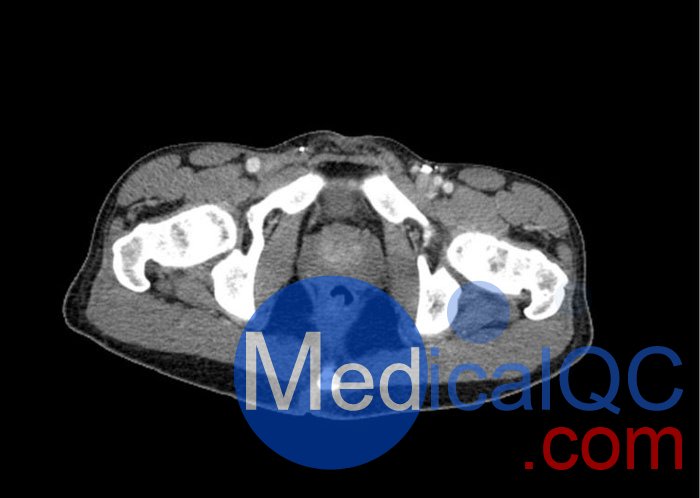

WEK57-01門靜脈期軀干模體,WEK57-01軀干模型模擬了門靜脈期的造影劑增強(qiáng)胸部、腹部和骨盆。它覆蓋了會陰的第二胸椎。

右側(cè)有髂淋巴結(jié)腫塊。

該模型可用于 CT(包括 CBCT)以評估和優(yōu)化成像性能和后處理應(yīng)用,包括支持 AI 的應(yīng)用。它也適用于培訓(xùn)目的。

該模型提供了對軟組織和骨組織的詳細(xì)而逼真的模擬。包括肺在內(nèi)的空隙充滿了大約 -160HU的纖維素聚合物復(fù)合材料。

真實模擬脈管系統(tǒng)、骨骼和軟組織,包括肺、心臟、肝臟、膽囊、胰腺、脾臟、腎上腺、腎臟、胃、小腸、結(jié)腸、膀胱和前列腺。

右側(cè)髂外淋巴結(jié)腫塊。

WEK57-01門靜脈期軀干模體,WEK57-01軀干模型成像效果圖: